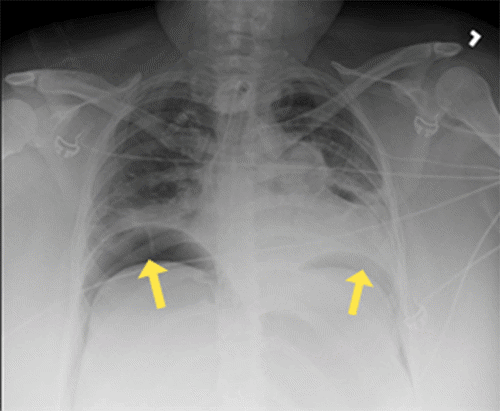

Within 30 minutes of arrival to the SICU, the patient’s abdomen was noted to be distended and firm. Her peak inspiratory pressures (PIP) were elevated, ranging between 55 to 60, and she was hypoxic with oxygen saturation in the 70s and 80s. Arterial blood gas (ABG) revealed a pH of 7.32, PaCO2 of 70, and bicarbonate level of 35. The PAO2/FiO2 ratio was 87. A chest X-ray (CXR) (Figure 1) showed the tracheostomy tube placed in the right mainstem bronchus. An urgent bedside tracheostomy exchange was performed by the ENT, replacing the tube with a shorter one. A subsequent CXR also revealed pneumoperitoneum, with free air observed under both hemidiaphragm, a finding that was confirmed by abdominal X-ray (AXR) (Figure 2).

Figure 2. Postoperative Abdominal X-ray. Published with Permission

Imaging confirms the presence of free intraperitoneal air